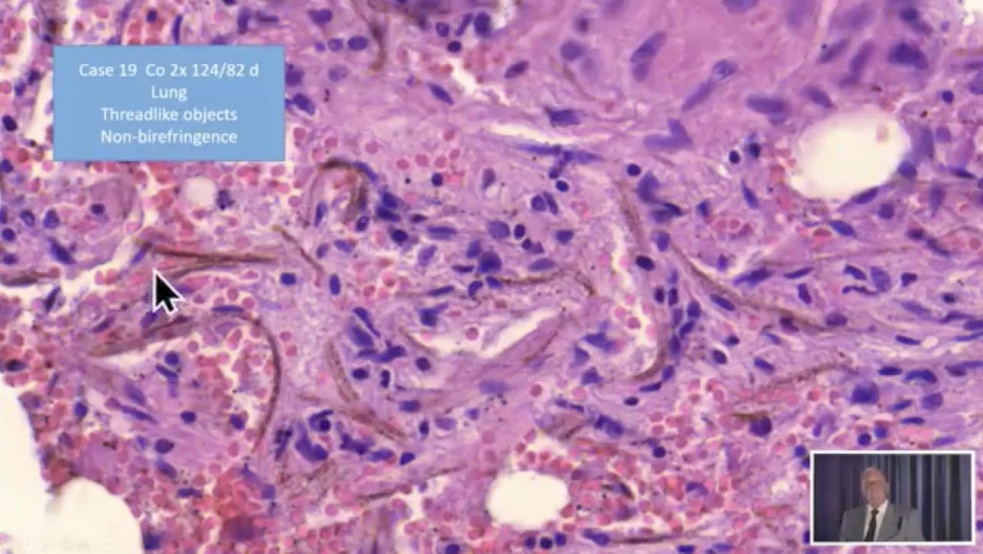

Video 9.10.2021: Pfizer

vaccine=toxic agent! -

Pfizer-Impfstoff=Kampfstoff! Objekte+Fäden

(25''): https://www.bitchute.com/video/YqnKldt4iyOH/

Pfizer-Impfstoff=Kampfstoff! (25'')

Link: https://www.bitchute.com/video/YqnKldt4iyOH/

- Bitchute-Kanal: NatMed-etc. - hochgeladen am

10.10.2021